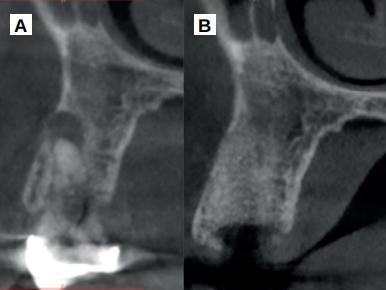

Cinco meses tras la colocación del implante, se realizó la toma de impresiones para la realización de una corona cemento-atornillada sobre una base de titanio. Un año tras la colocación de la corona, se observó el buen aspecto gingival (Figura 14) y radiográfico, donde se observa una pérdida ósea marginal fisiológica en las radiografías periapicales (Figura 15), y en los cortes del CBCT (Figura 16).

Por último, las dimensiones óseas pueden ser mantenidas de manera favorable cuando se emplea el diente como biomaterial en procedimientos de preservación alveolar, con una tasa de reabsorción aparentemente baja, siendo de esta manera un procedimiento predecible, con parámetros de pérdida ósea marginal fisiológicos tras un año de carga prostodóncica.

B. Corte sagital al año de la carga prostodóncica.